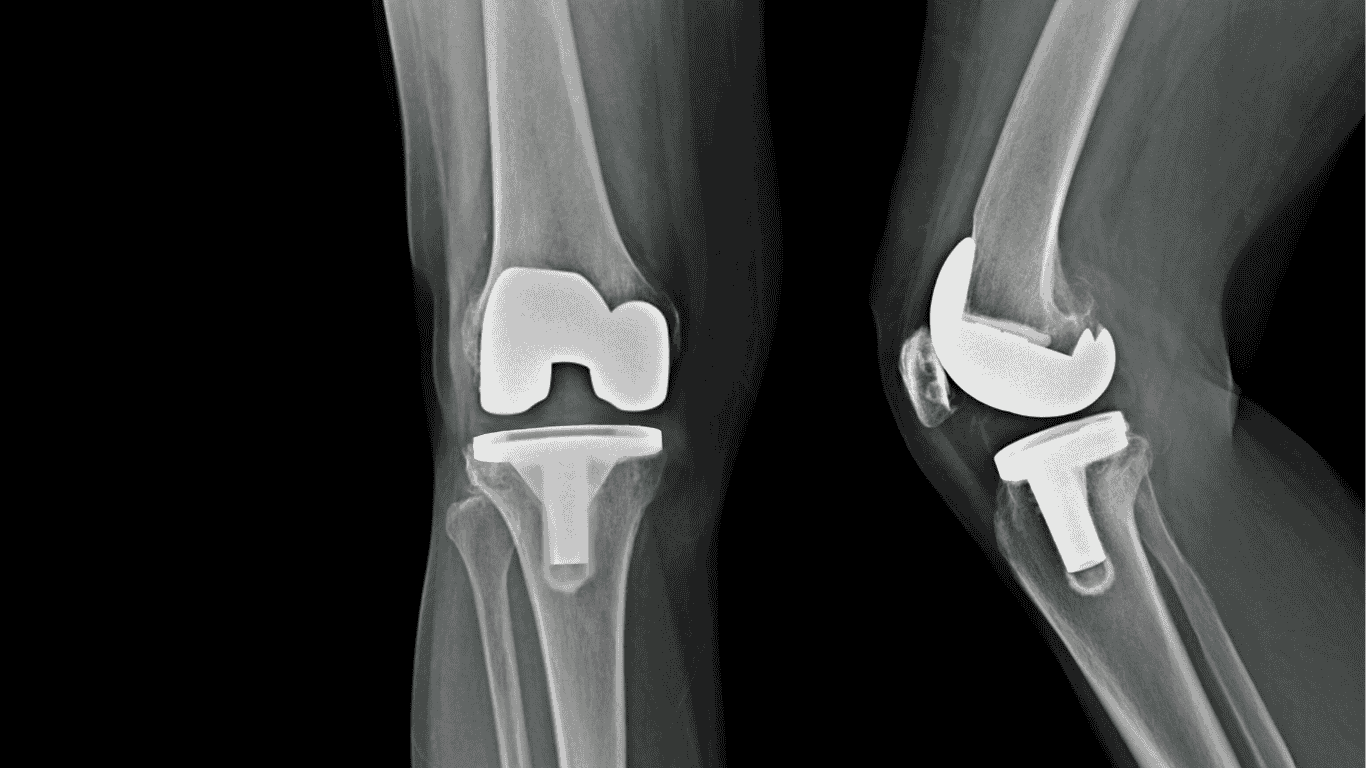

ألم بعد عملية تغيير مفصل الركبة: لماذا يحدث وكيف تتغلب عليه بسرعة؟

تُعدّ عملية تغيير مفصل الركبة واحدة من أنجح الإجراءات الجراحية الحديثة لعلاج تآكل المفصل وتحسين القدرة على الحركة، ولكن يبقى السؤال الأكثر شيوعًا لدى المرضى: لماذا أشعر بـألم بعد عملية تغيير مفصل الركبة؟ وهل التورم طبيعي؟ ومتى يبدأ الألم في التحسن؟